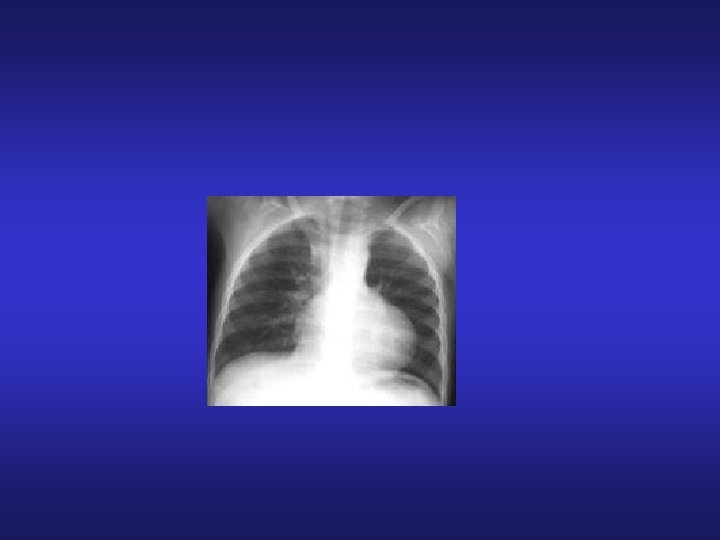

TOF Klinik Bulgular EKG • Sağ aks deviasyonu mevcut (Pink Fallot’da aks normal) • Sağ ventrikül hipertrofisi Teleradyografi Pulmoner vasküler gölgelenmede azalma Coeur en Sabot- PA segmentinde konkavlık, apeks ucu kalkmış Ekokardiyografi VSD, Ata binen aorta, pulmoner darlık, koroner arter anatomisi kaba değerlendirmesi